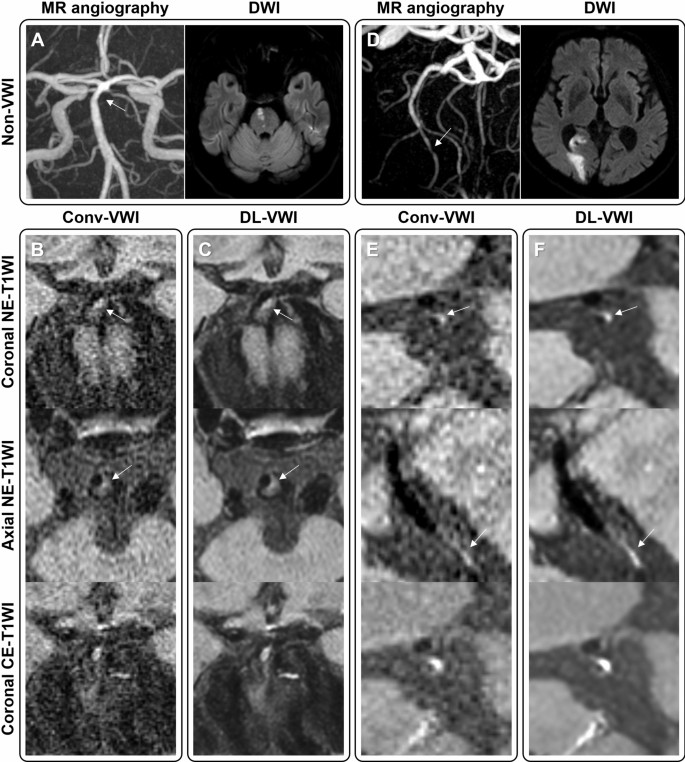

Figure 4 demonstrates better depiction of the culprit plaque characteristics on DL-VWI. DL-VWI was also helpful in detecting subtle plaque enhancement (Fig. 5) and lesions in severely motion-degraded images (Supplemental Fig. 4). Identification of dissection, especially differentiating it from atherosclerosis, was more confidently performed when nonenhanced and contrast-enhanced DL-VWI were available (Supplemental Figs. 5, 6). Another example culprit lesion containing IPH was used to measure signal profiles, both on NE-T1WI and CE-T1WI (Fig. 6).

Two illustrative cases of potentially culprit plaques. (A) In a 62-year-old male with abrupt dysarthria and pontine infarct, only mild distal basilar stenosis was identified on MR angiography. (B) Conv-VWI revealed the plaque with punctate T1WI hyperintensity, which was interpreted as an intraplaque hemorrhage (IPH) by only one reviewer. (C) DL-VWI more clearly depicts the apparent T1WI hyperintensity and positive remodeling. (D) Another 66-year-old male presented with abrupt left homonymous hemianopia, showing right posterior cerebral artery territory infarct with focal distal stenosis. (E) Same as Fig. 1, the signal of the plaque in Conv-VWI was misinterpreted as image noise by both reviewers. (F) DL-VWI provides a clearer depiction of the presence of IPH.

A 71-year-old female with a segmental atherosclerotic plaque along the 1st segment of the left middle cerebral artery. The shape of the wall lesion is more clearly delineated in DL-VWI (D–F) than in Conv-VWI (A–C). In contrast-enhanced Conv-VWI (B and C), contrast enhancement is not clearly seen due to the background noise of the vessel wall and brain parenchyma. However, contrast-enhanced DL-VWI (E and F) clearly depict subtle enhancement at the distal portion of the wall lesion.